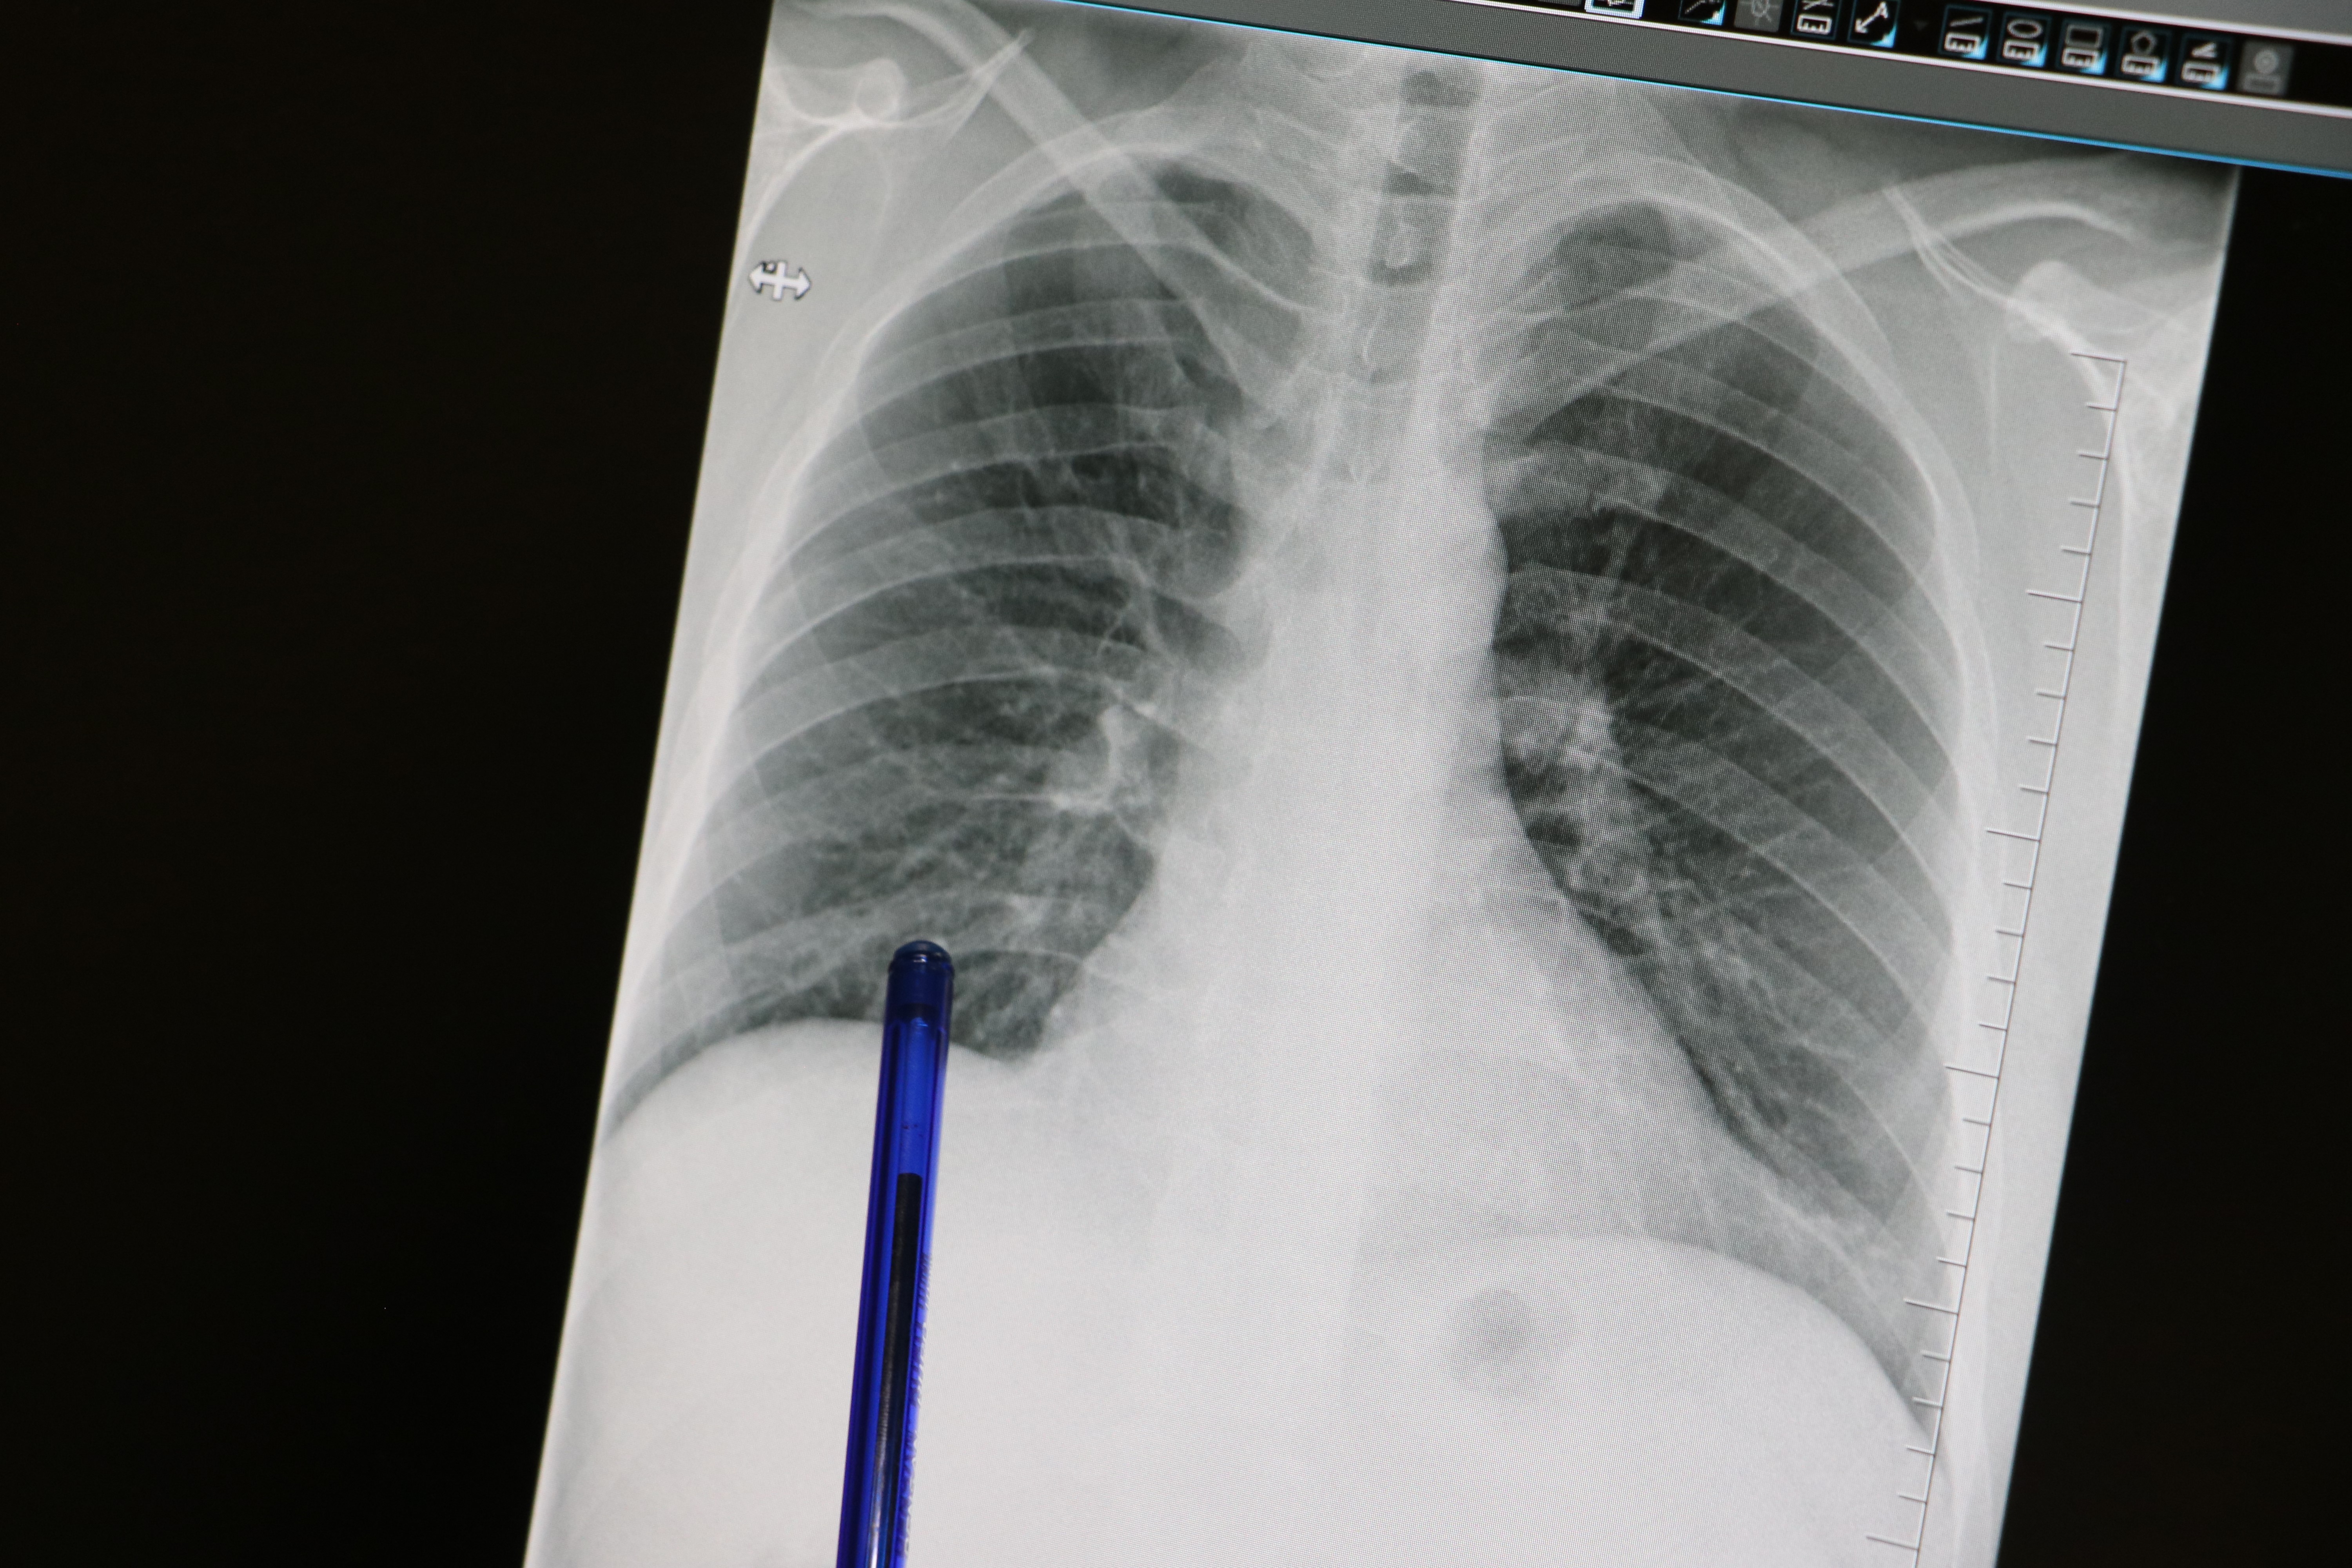

Sürekli Öksürük Hayati Tehlike Taşıyor

COVID Varyantları Yeniden Gündemde: Hastanelerde Yoğunluk Artıyor